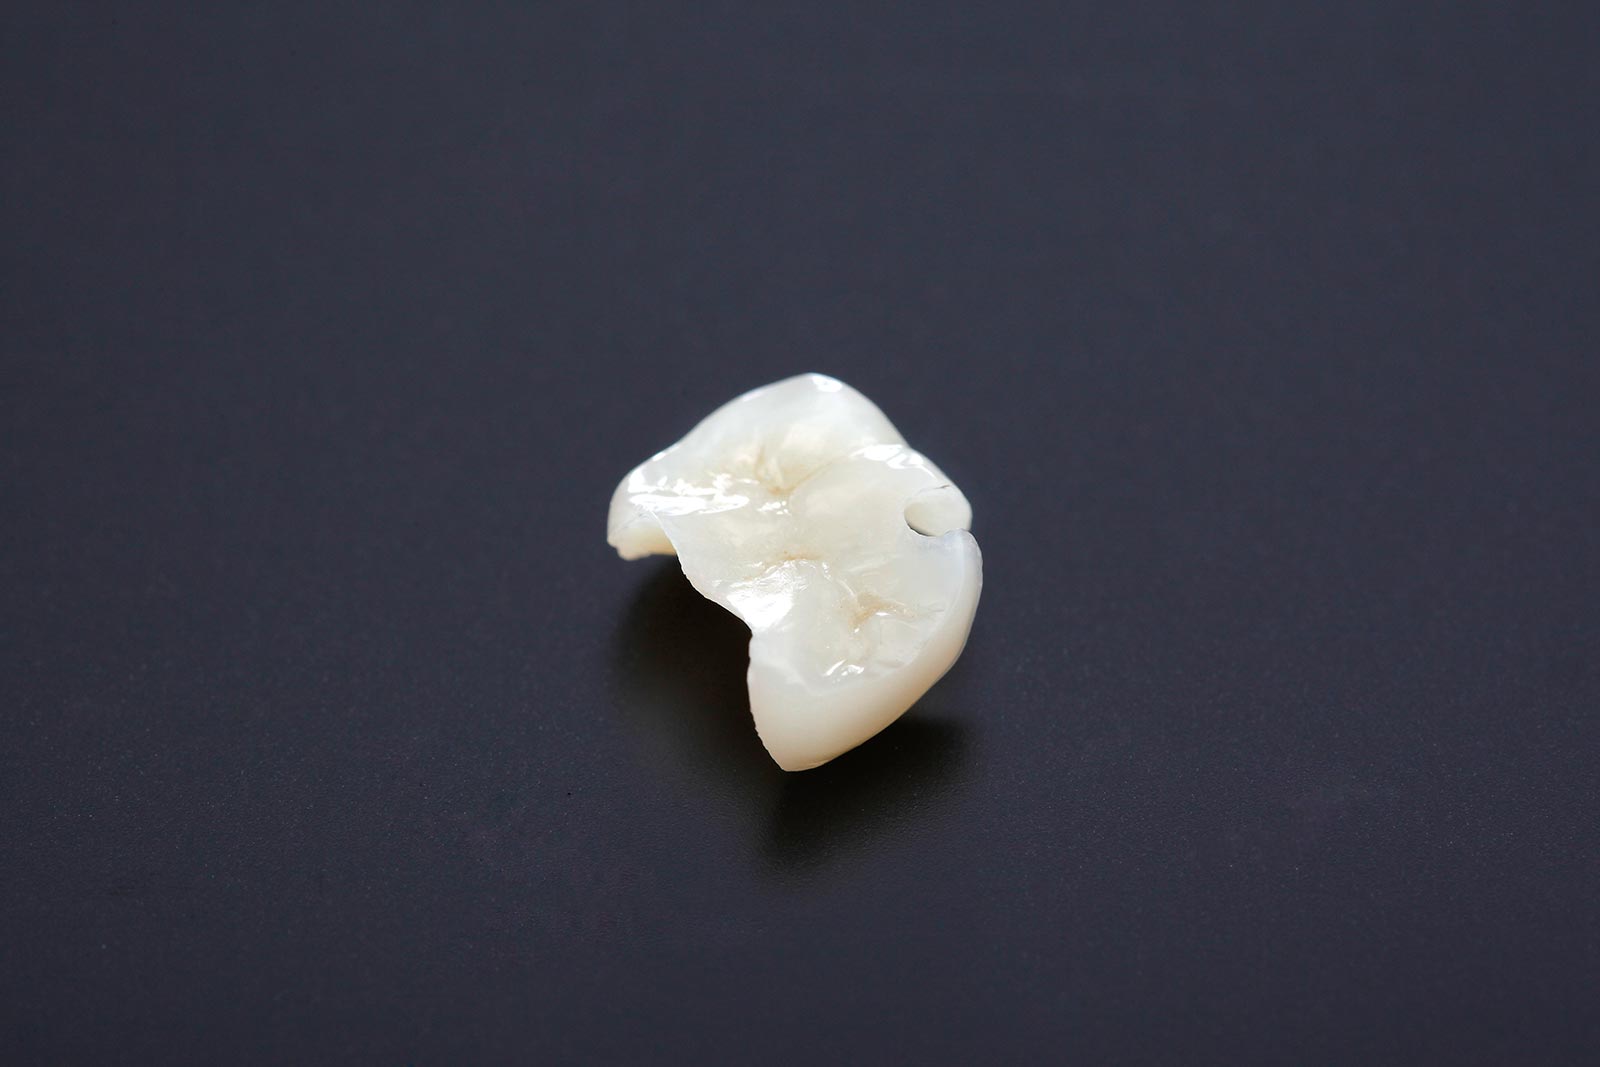

被せ物はあくまでも人工物です。歯科治療では、こうした人工物を天然の歯に装着するのですが、どうしても歯と被せ物の間には隙間が生じてしまいます。

この隙間から、虫歯菌が入り込んでしまうと、被せ物の中で虫歯菌が増殖し、虫歯になってしまいます。気がつけば、被せ物の下で虫歯が進行していたというケースは珍しくありません。

次の画像を見てください。

外見からは虫歯であることが分かりませんが、詰め物を外すと、中で虫歯が進行していました。

治療時に、この隙間を作らないようにすることで、虫歯を予防し、治療した歯を長くもたせることができます。虫歯治療の成否を分けると言っても過言ではないでしょう。

しかし、隙間は目では確認できないレベルの幅しかありません。これを目視で行うのは不可能で、当院では隙間の調整を高倍率拡大鏡などを使って行います。これによって、長く使い続けられる被せ物などの処置が可能になるのです。